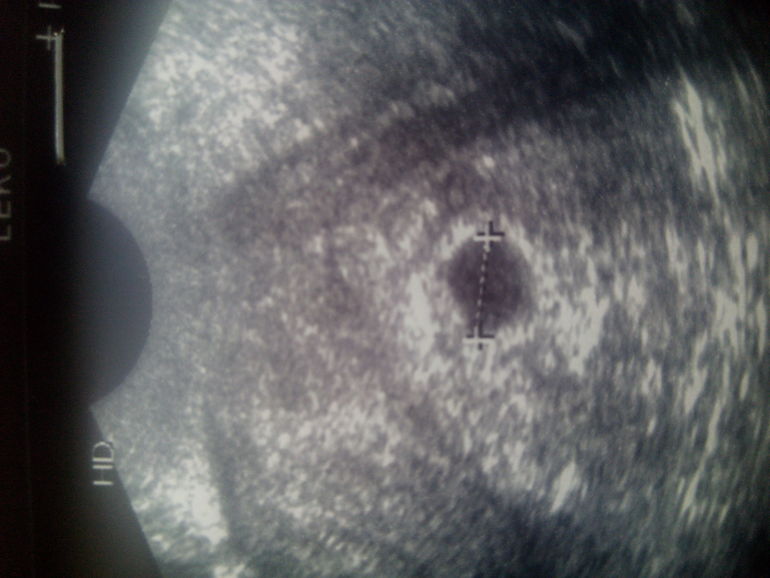

Беременность- 1 триместр ( только до 10 недель)Б маточная 3-4 недели эмбр. Размер пл.я. 11 мм. Узистка, по совместительству моя будущая врач в жк, мне не понравилась. Она ничего не говорила, только показала монитор, а все писала на бумажку. Ла и вообще она какая-то злюка.

А вот и мы. На нижнем фото мне кажется я вижу эмбриончик возле нижнего поюсика.